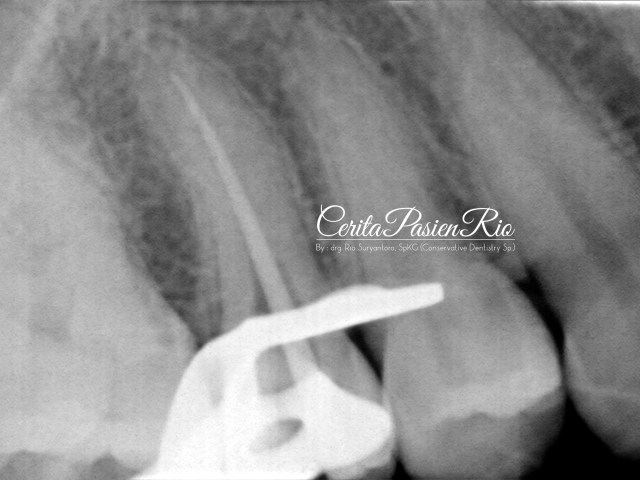

Gambar 27. evaluasi radiograf dengan foto xray dental yang dilakukan pasca penambalan. tampak integritas tepi resin komposit yang rapat dan homogenitas dari restorasinya yang padat.